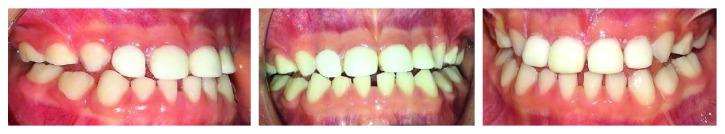

The prevalence of class III malocclusion ranged from 0 to 26% in different populations. Many types of treatments have been described in dental literature. The results of early treatment have been positive. The purpose of this report is to describe the case of a four-year-old patient with class III malocclusion who received an innovative treatment using direct anterior tracks. This therapy efficiently obtained immediate improvement of profile and occlusal relationships.

在不同人群中,III类错牙合畸形的患病率在0%至26%之间。牙科文献中描述了多种治疗方法。早期治疗的结果是积极的。本报告的目的是描述一名患有III类错牙合畸形的四岁患者的病例,该患者接受了使用直接前方导板的创新治疗。这种治疗有效地立即改善了面部轮廓和咬合关系。